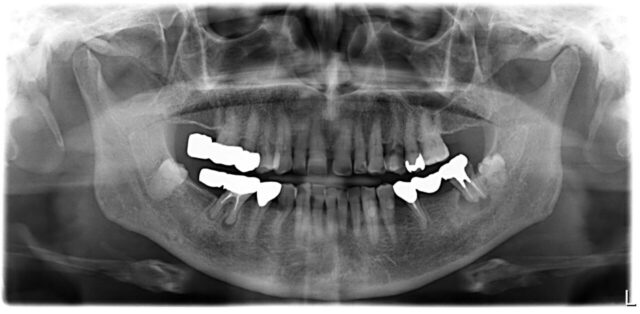

Before

| 主訴 | 奥歯の痛みと腫れ |

| 年齢 | 60代 |

| 性別 | 男性 |

| 治療期間・回数 | 9ヶ月 14回 |

| 治療方法 | 下顎大臼歯の抜歯と仮義歯製作,インプラント補綴 |

| デメリット・注意点 | 抜歯後の治癒期間も必要で治療完了まで長期間かかりました.その間は仮義歯を製作し使用してもらいました. |